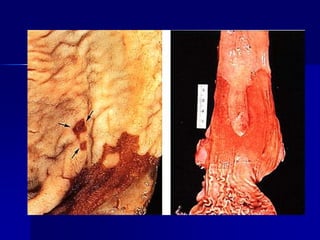

Una mujer de 74 años con sangre oculta

en las heces tiene un nivel de hematocrito

de 35,7% (nl 35% a 46%), un MCV de 79

fL [fL=fentolitro=10-15 L] (nl 78 a 102 fL),

y recuentos de plaquetas y glóbulos

blancos normal . Se muestran los

hallazgos pertinentes en la colonoscopia.

1. ¿Cuáles son los dos diagnósticos que

puedes hacer?

2. Explique los hallazgos de laboratorio.